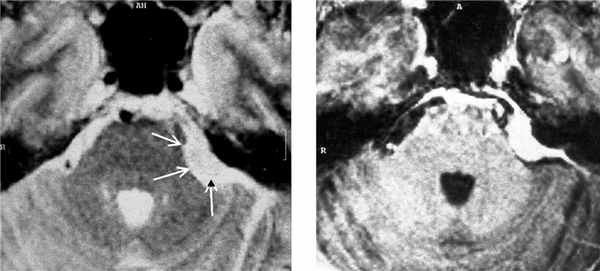

Менингиома вторая по частоте опухоль мосто-мозжечкового угла после невриномы VIII пары. Как и при других локализациях менингиома чаще встречается у женщин среднего возраста. Мелкую, расположенную внутри канальца менингиому, при МРТ невозможно отличить от невриномы. Однако, внутриканальцевый компонент больше характерен для неврином. Крупная менингиома при МРТ головного мозга имеет типичное для этих опухолей плоское основание и соответственно форму полукруга, часто распространяется в среднюю черепную ямку. Интенсивность сигнала от менингиомы на Т2-взвешенныъ МРТ обычно ниже, чем от невриномы. Структура опухоли при МРТ может быть как однородной, так и гетерогенной. В пользу менингиомы говорит прорастание верхушки пирамиды, разрушение ее структуры с элементами склероза. Невринома и нейрофиброма продавливают и ампутируют верхушку пирамиды. В дифференциальной диагностике помогают и другие МРТ признаки, типичные для менингиом: симптом “хвоста”, ликворное кольцо и смещение сосудов. Контрастирование МРТ усиливает сигнал от менингиомы также хорошо, как и от невриномы.

МРТ головного мозга. Менингиома мостомозжечкового угла (стрелки). Аксиальные Т2-зависимая МРТ и Т1-зависимая МРТ с контрастированием.